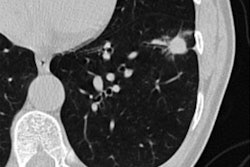

Computer-aided diagnosis (CAD) using deep learning shows potential for improving the ability of readers to identify and classify lung nodules on CT imaging, according to a literature review published August 25 in Computers in Biology and Medicine.

"Physicians can diagnose lung cancer by analyzing the pulmonary nodules in CT images, but this task is taxing ... and factors such as inattention, fatigue, and lack of relevant work experience may affect the results," the authors noted. "Computer-aided diagnosis technology has been developed to relieve the pressure on physicians and improve the accuracy and efficiency of diagnosis."

Lung cancer is one of the most fatal cancers, but annual low-dose CT screening for the disease for those at risk has been shown to decrease mortality rates by 20%, Gu and colleagues wrote. Could computer-aided diagnosis technology improve that rate even more by helping clinicians with the reading workload and improving accuracy? The investigators sought to find out.